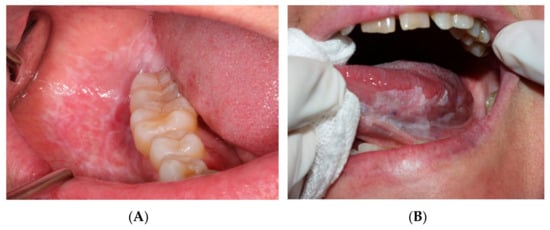

The control group, in turn, consisted of healthy individuals of similar age and habits that visited the dental clinic (Oral Medicine Unit) during the same period for other types of benign oral pathology, such as mucocele or benign tumors, without any sign or history OPMD (Figure 1 and Figure 2).

Figure 2.

Potentially malignant oral lesions. (A) Oral lichen planus on the buccal mucosa. (B) Oral leukoplakia on the ventral surface of the tongue.